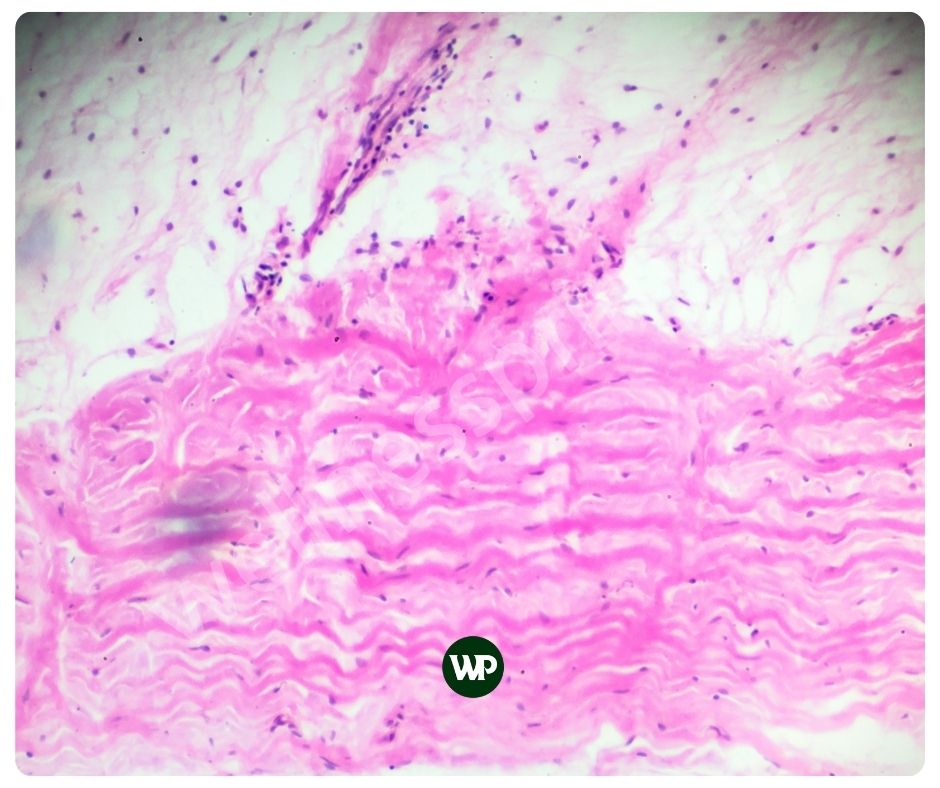

엘라스틴은 결합 조직의 주요 구성 요소 중 하나로, 피부, 폐, 동맥 벽 등 다양한 신체 부위에서 존재합니다. 이 단백질은 조직에 탄력성과 유연성을 부여하여 피부가 부드럽고 탄력 있게 유지되도록 돕습니다.